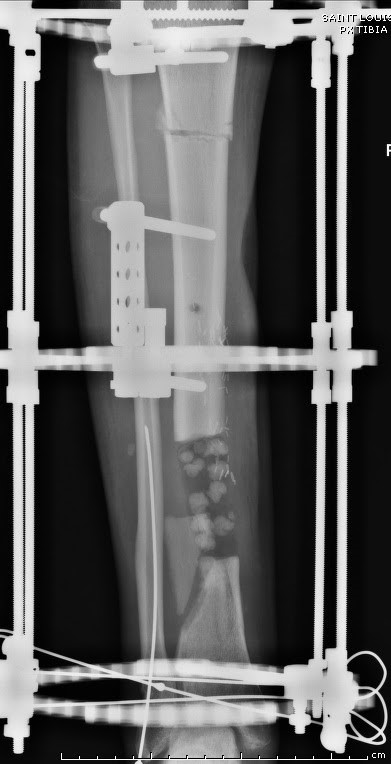

Данный случай не огнестрельная рана, а результат мотоциклетной аварии.

Независимо от повреждения при таких обширных дефектах мягких и костной

тканей применяется схожая тактика. Как видно, после нескольких I&D для

создания “pseudo membrane” применили цилиндрический блок из цемента.

Дефект мягких тканей закрыли свободным Anterior Thigh Graft. Из малого

доступа цилиндр удален небольшими кусочками, а пространство заполнили

бусами для освобождения пространства. По мере приближения регенерата

освободили пространство удалением бус через небольшой разрез. Этап

созревание регенерата можно было ускорить усилением интрамедуллярным

гвоздем, но решили закончить методом Илизарова.